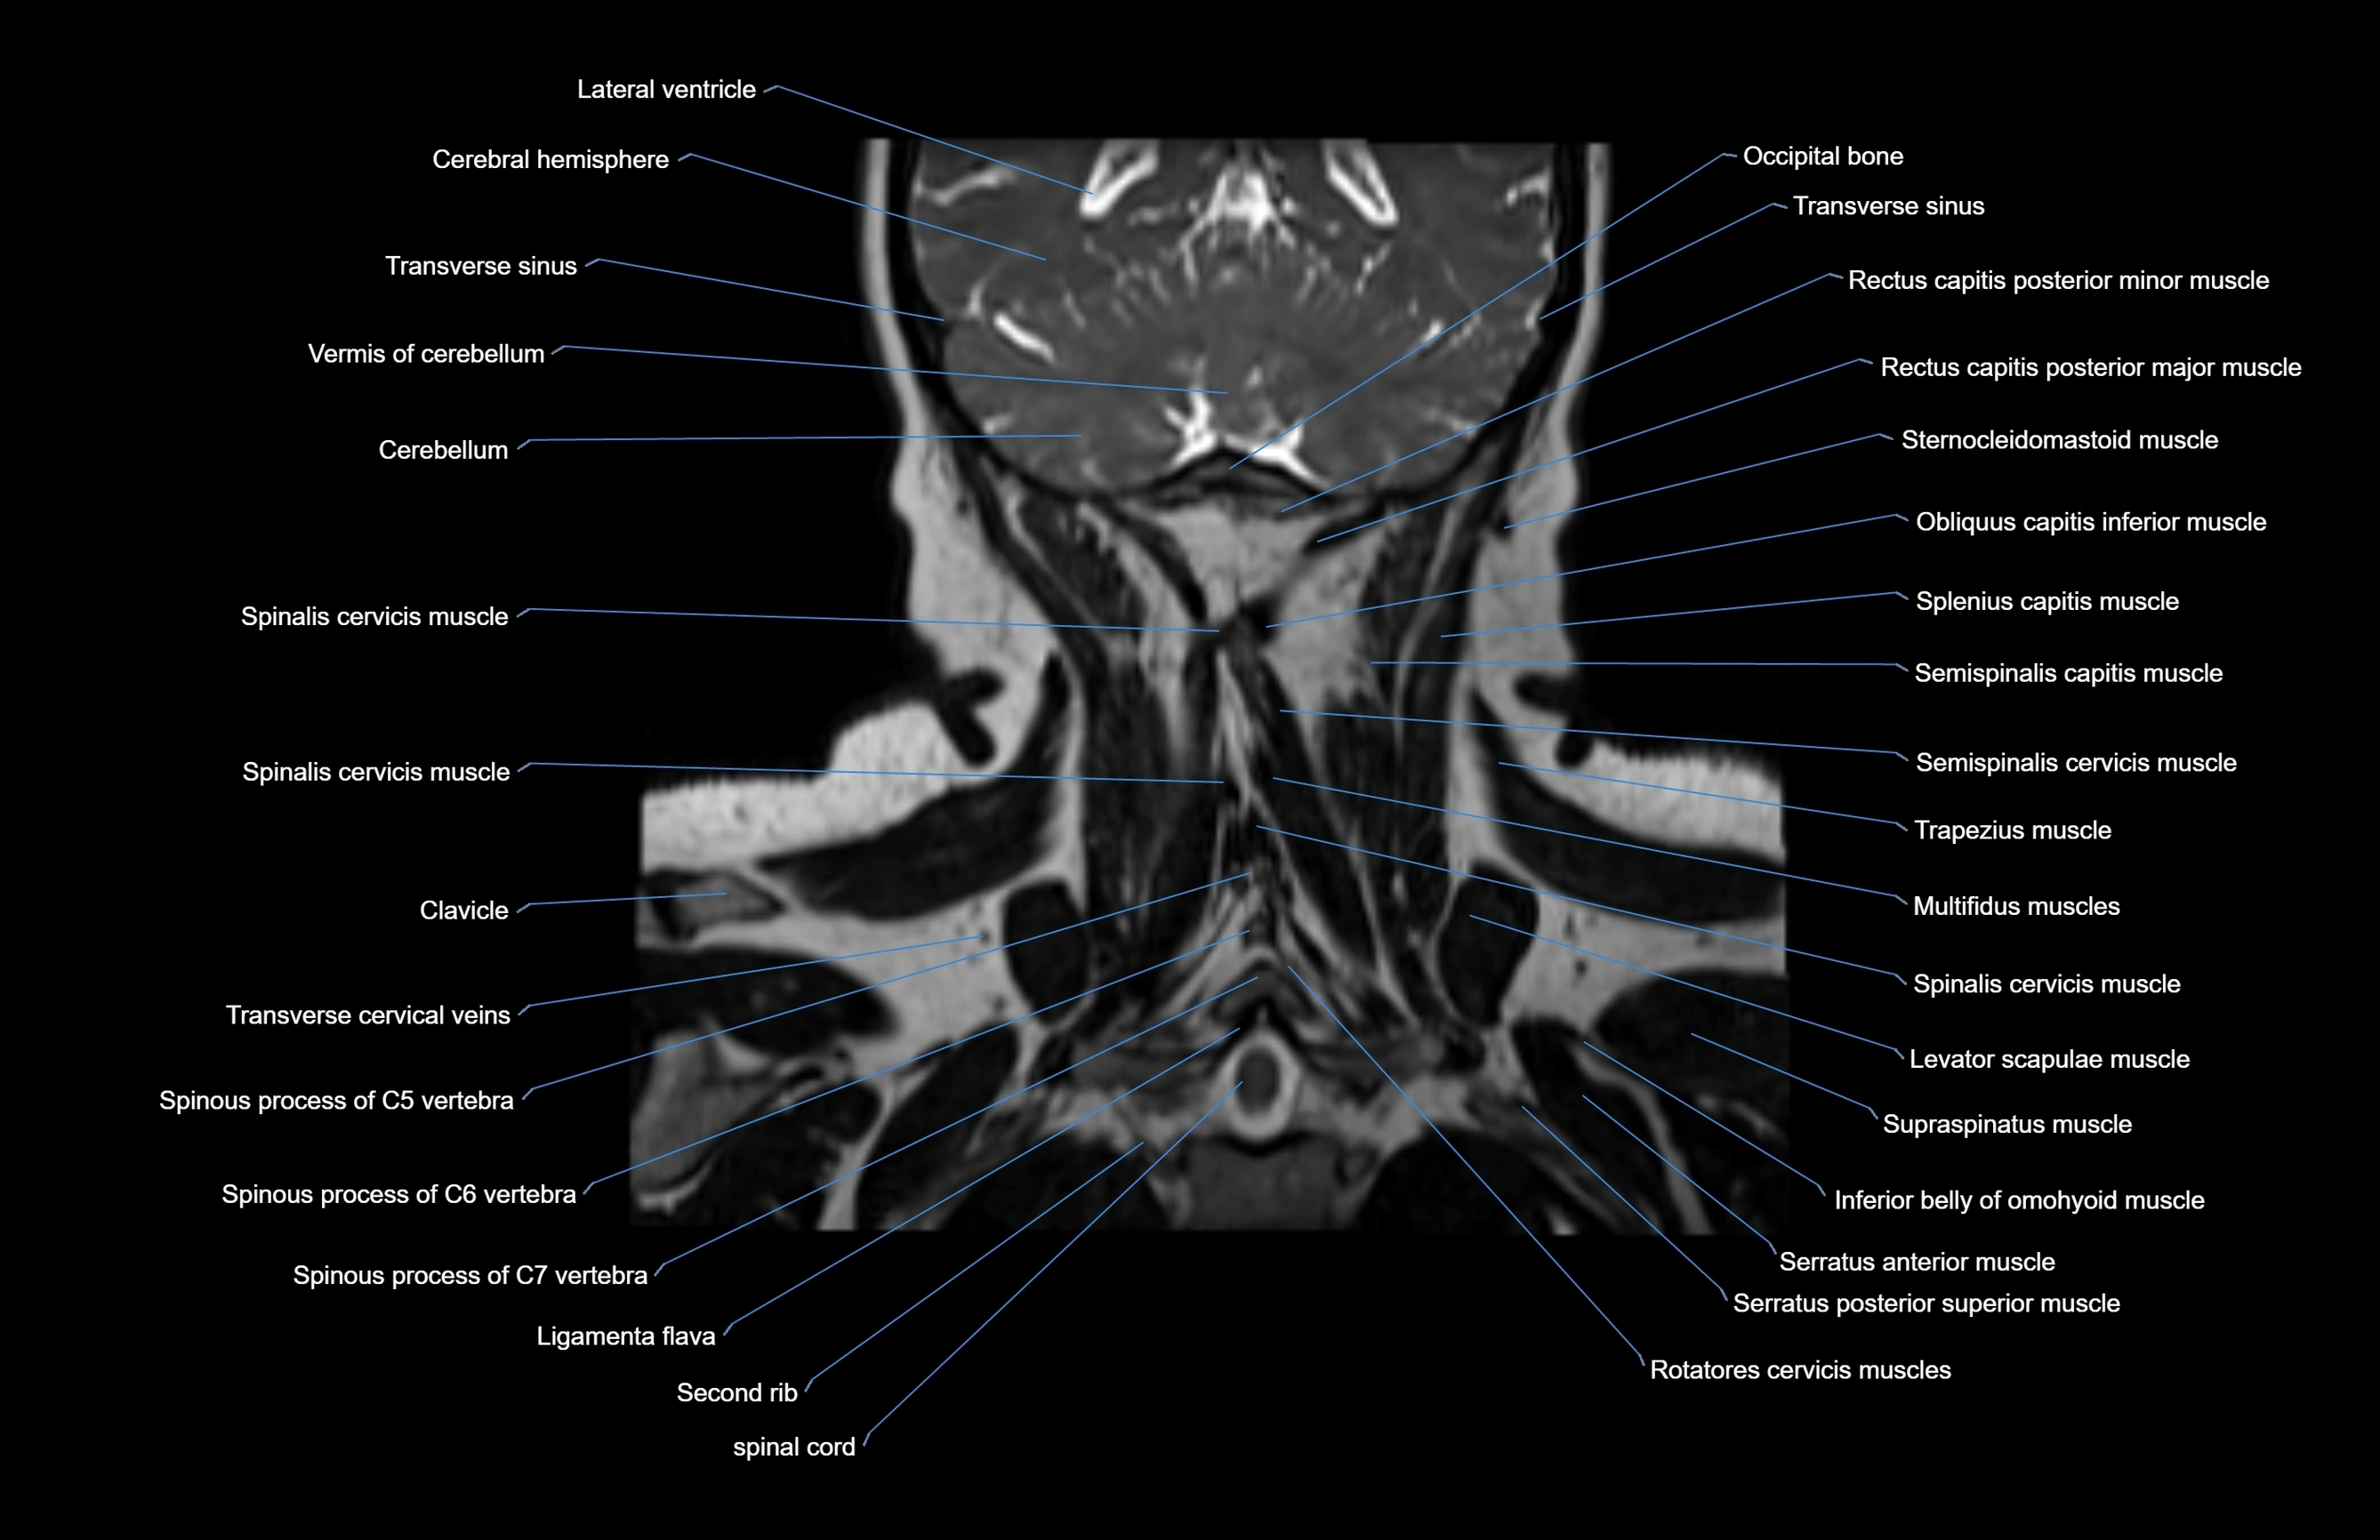

MRI images